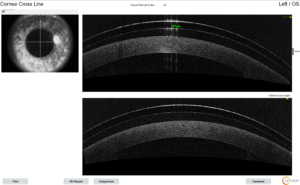

What is Corneal Crosslinking for Keratoconus?

Keratoconus is a disease marked by a progressive corneal thinning which can lead to distorted vision. Traditional treatment for keratconus includes glasses until not tolerated, corneal gas permeable contact lenses, and eventually corneal transplant. Newer treatments include scleral contact lenses and corneal crosslinking. Is My Keratoconus Going to Get Worse? Most people